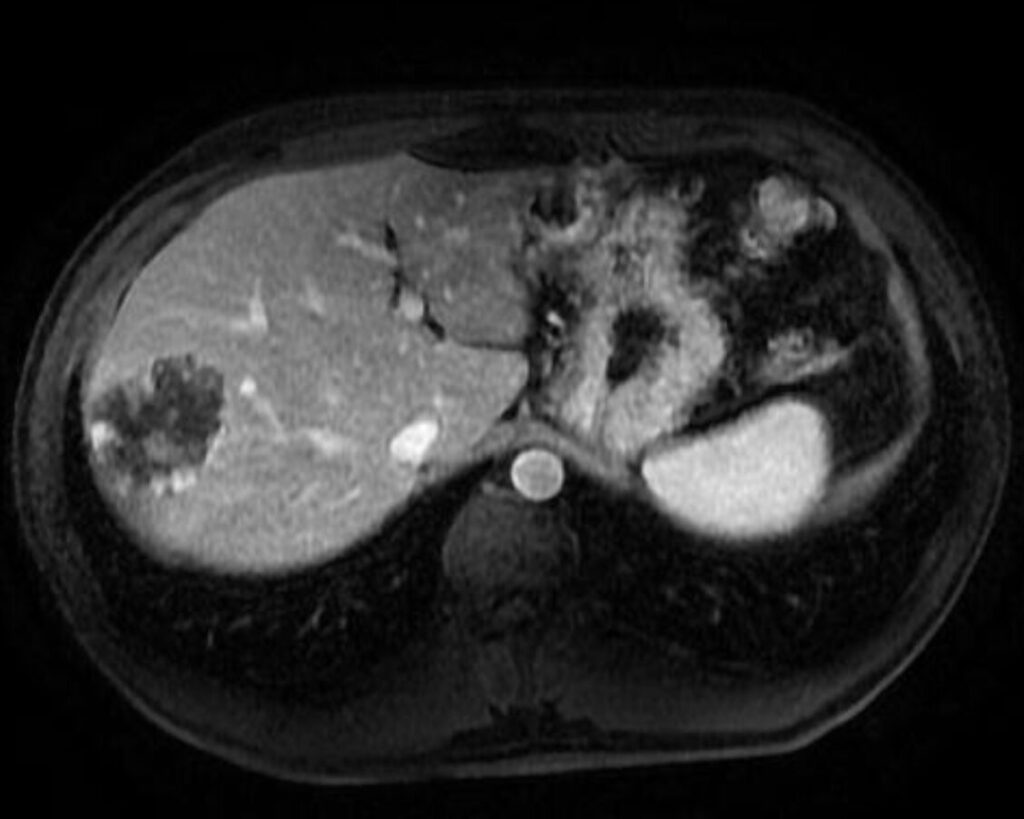

ANGIOMA CAVERNOSO

Lesione epatica benigna più comune, con rapporto F:M di 5:1.

Spesso di dimensioni ridotte, può essere anche di diversi centimetri (> 10 cm si parla di ‘’angioma gigante’’).

Aspetto RM

- Alterazione focale iso-ipointensa in T1, marcatamente iperintensa in T2, caratterizzata da un rapido e omogeneo enhancement in fase arteriosa senza wash-out, con ipointensità in fase epatospecifica.